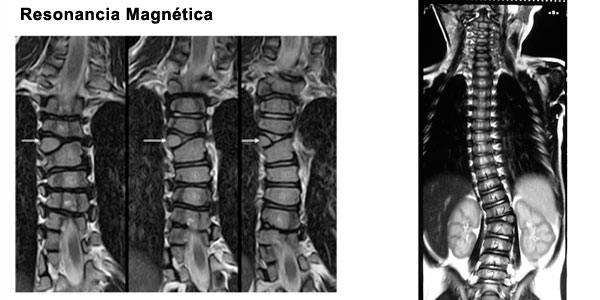

Al tener un diagnostico de escoliosis congenita debe descartarse otras malformaciones en otros organos y/o sistemas:

Anomalias intraespinales.

Es necesario evaluar con detalle al niño y solicitar estudios de imágenes que nos puede mostrar la estructura de la columna en forma completa.